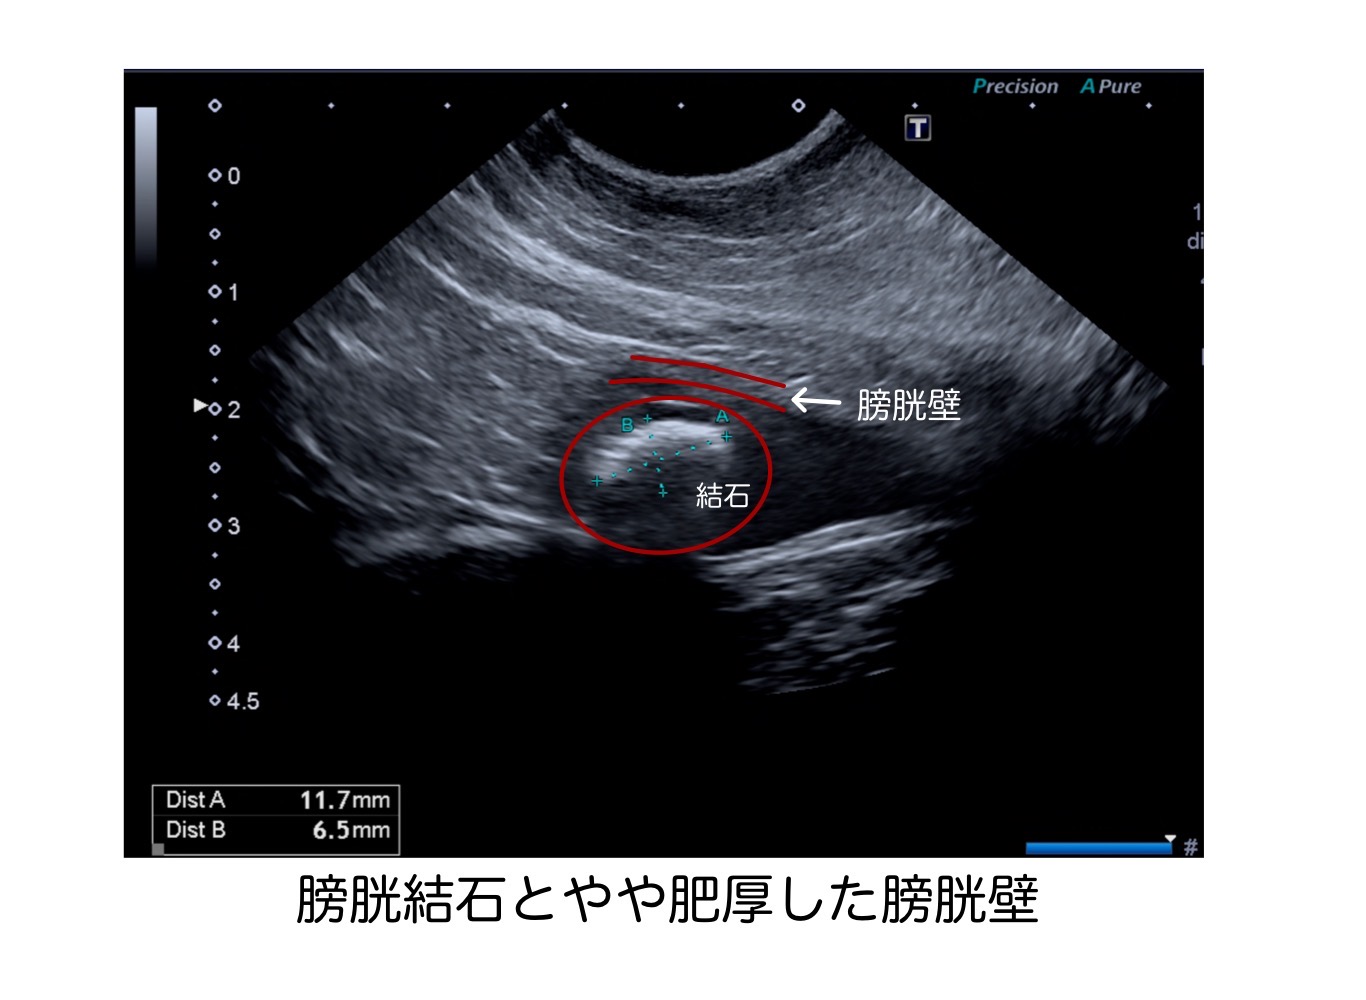

こちらが、手術前のレントゲン検査と超音波検査の結果です。

今回、尿漏れ、頻尿、血尿を繰り返している15歳の猫ちゃんの⒈3cm大の膀胱結石を腹腔鏡下にて摘出しました。